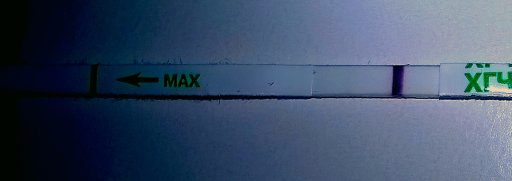

10-11дпо

Купила вчера тест мне неизвестный

Первый ответ Ева

вроде как он реагентит?

ну и видите что-нибудь?

На счет Евы не знаю, а вот пресловутый Будьте Уверены не бери, омно полное. А так вроде что то есть, сделай еще какой нибудь)

Эти тесты так рано не показывают. Так что реагент. Да и по фото видно, что это он